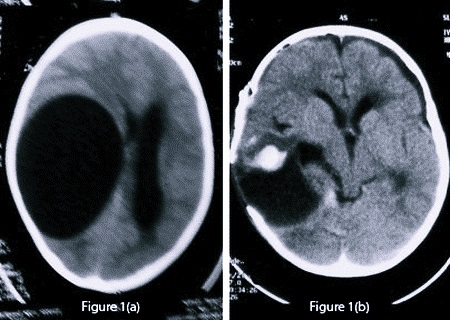

image

Использование УЗИ позволяет выявить некоторые врожденные кисты еще в период внутриутробного развития, после рождения ребенка и до закрытия его большого родничка диагностика возможна при помощи нейросонографии. В дальнейшем визуализировать кисту можно посредством КТ или МРТ головного мозга. Для дифференцировки кистозного образования от опухоли мозга эти исследования проводят с контрастированием, поскольку в отличие от опухоли, киста не накапливает в себе контрастное вещество. Для лучшей визуализации кистозной полости возможно введение в нее контраста путем пункции кисты. В отличие от МРТ, КТ головного мозга дает возможность судить о вязкости содержимого кисты по плотности ее изображения, что учитывается при планировании хирургического лечения. Основополагающее значение имеет не только установление диагноза, но и непрерывное наблюдение за кистозным образованием для оценки изменения его объема в динамике. При постинсультном генезе кисты дополнительно прибегают к сосудистым обследованиям: дуплексному сканированию, УЗДГ, КТ или МРТ сосудов головного мозга.

Консервативная терапия малоэффективна. Лечение возможно только хирургическим путем. Однако большинство кист не нуждаются в активном лечении, поскольку имеют малый размер и не прогрессируют в размере. В отношении их проводится регулярное динамическое наблюдение при помощи МРТ- или КТ-контроля. Нейрохирургическому лечению подлежат кисты, клинически проявляющиеся симптомами гидроцефалии, прогрессивно увеличивающиеся в размере, осложненные разрывом, кровотечением, сдавлением мозга. Выбор метода операции и хирургического подхода осуществляется на консультации нейрохирурга.

В случаях тяжелого состояния пациента с расстройством сознания (сопор, кома) в экстренном порядке показано наружное вентрикулярное дренирование для уменьшения внутричерепного давления и сдавления мозга. В случае развития осложнений в виде разрыва кисты или кровоизлияния, а также при паразитарной этиологии кисты хирургическое вмешательство выполняется с целью радикального иссечения кистозного образования; хирургическим доступом является трепанация черепа.